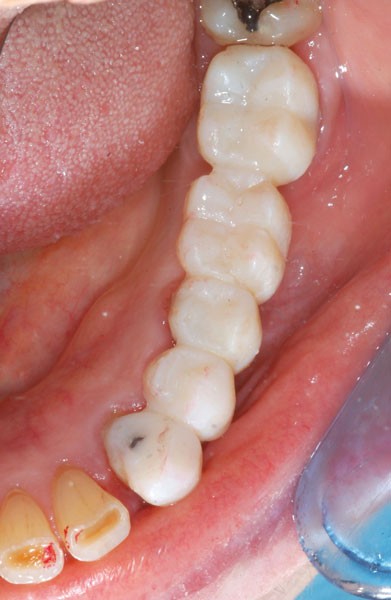

L’automoulage est garni avec une résine composite (Protemp™ 4, 3M ESPE), avant ajustage et finition (roues spirales Sof-Lex™, 3M ESPE), pose du bridge transitoire.